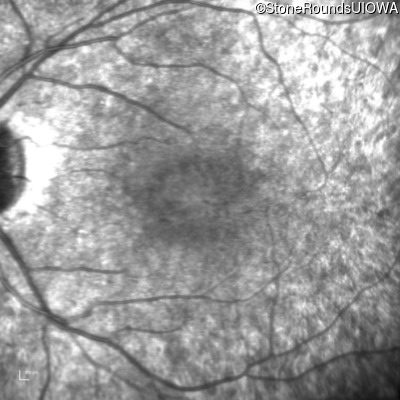

Age at visit: 7 years

OD OS

This 7 year old girl has had very poor vision in dim light and slightly subnormal acuity her entire life.